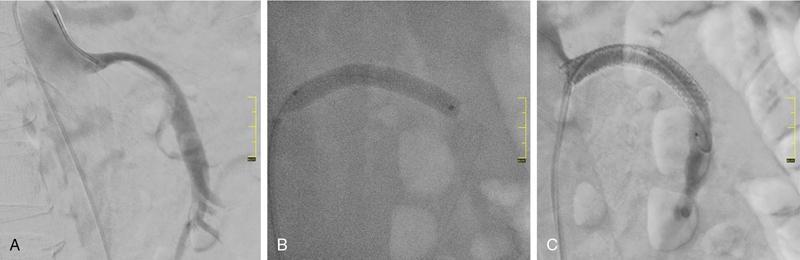

Munawwar Ahmed, Vikash Jain, Santhosh Babu K.B.,Shyamkumar N. Keshava Vascular interventions of gastrointestinal tract include recanalization and occlusive procedures. These are minimally invasive techniques, which play a role both in elective and emergency situations. Traditionally interventional radiological options have been considered as an alternative to the established surgical treatment options; however, currently many of these procedures have become the primary therapeutic option. In this chapter, we have discussed a few common conditions with case illustrations. Mesenteric ischaemia (MI) is an uncommon clinical condition caused by inadequate splanchnic blood flow to intestine (Table 7.17.1). MI can be acute or chronic as follows: SMA supplies largest part of the intestine including both small and large intestines and receives approximately 15%–20% of cardiac output in normal condition which increases to approximately 35% within 20 minutes of meal because of the increased oxygen demand. Small intestine can tolerate 75% reduction in blood supply for up to 12 hours (due to extensive mesenteric collaterals and auto-regulation) and bowel infarction or irreversible damage can develop in a minimum 6 hours of complete occlusion. Mucosa of the bowel is the most susceptible layer and affected first. Ischaemic bowel injury ranges from reversible mucosal injury to transmural infarction and necrosis. With intestinal necrosis there is bacterial translocation, robust inflammatory response resulting in cytokine storm which may cause profound hypotension, multiorgan failure, septic shock and even death. Reperfusion injury may occur following therapy secondary to formation of reactive oxygen species from interaction between oxygen rich blood and free radicals locally produced during inflammatory response. It may further lead to cell death through direct injury to cell membrane and proteins. Patients with CMI typically present with insidious onset of postprandial abdominal pain with associated significant weight loss. Pain typically starts 20–30 minutes after meal and lasts for 1–2 hours. Given the association of pain with food intake often leads to food aversion. Nonspecific symptoms are nausea, vomiting, diarrhoea and constipation. It is commonly seen in elderly (>60 years) smokers and unlike other atherosclerotic diseases, females are three times more likely to be affected. This is likely secondary to differences in the orientation of the mesenteric vessels to the aorta, with a more acute angle to the aorta in females when compared to males. The likely result is altered flow dynamics and increased susceptibility to atherosclerotic disease. Patients with mesenteric arterial stenosis may be asymptomatic due to presence of good collateral supply between mesenteric arteries (Fig. 7.17.1) and often require severe stenosis or occlusion of two or more proximal mesenteric arteries, more specifically SMA for clinical manifestation. Prevalence of mesenteric artery stenosis is not uncommon and progressively increases with increasing age, from 6% at 40 year and 14% at 60 year to 18%–67% at 75 year and above. Atherosclerosis is the commonest aetiology and most of the patients will have diffuse atherosclerosis in other territories (carotid, coronary and peripheral arteries) also. Other less common aetiologies are vasculitis, fibromuscular dysplasia, dissection, radiation therapy for cancer, postsurgical intimal hyperplasia and collaterals secondary to median arcuate ligament (MAL) compressing CA. The diagnosis is based on combination of clinical symptoms and radiological evaluation of the mesenteric vasculature. The value of symptoms alone is limited for the prediction of the diagnosis of CMI. Moreover, identification of occlusive disease in the mesenteric arteries is not suggestive of mesenteric ischaemia without associated clinical symptoms. Classical triad of symptoms of CMI include postprandial abdominal pain, weight loss and abdominal bruit on clinical examination; however, it is seen in only 22% of cases and has low predictive value (60% probability). The presenting symptoms are abdominal pain (94%), weight loss (80%), food aversion (52%), nausea, vomiting (26%) and diarrhoea (24%). Intermittent abdominal pain can progress to more constant and prolonged pain. If left untreated, CMI has the potential to develop AMI. Clinical examination may reveal abdominal bruit in 17%–87% of cases and cachexia. Laboratory findings are nonspecific and may include anaemia, hypoalbuminemia. Objective of the imaging is to confirm the diagnosis, and exclude the other causes of abdominal pain which can mimic CMI such as chronic pancreatitis, gastro-duodenal ulcer, gastric or pancreatic malignancy, inflammatory bowel disease, irritable bowel syndrome, MAL compressing CA. Imaging helps in treatment planning and assessment of the arterial lesion in terms of length of stenosis/occlusion, number of arteries involved, collateral flow and possible aetiology (atherosclerosis, arteritis, dissection, etc.) (Fig. 7.17.2). Duplex ultrasonography (DUS) is often the initial imaging modality and used to assess proximal stenosis or occlusion of the CA and SMA. DUS provides physiologic flow data and can be performed in the fasting and postprandial states to detect haemodynamically significant stenosis. In the fasting state, the SMA possesses a high-resistance waveform characteristic of the splanchnic circulation while the CA demonstrates low resistance wave form characteristic of flow throughout the cardiac cycle within hepatic and splenic parenchyma. However, in the postprandial state, the SMA will show a marked increase in EDV with a less dramatic increase seen in the coeliac circulation. A significant stenosis (>70%) will be characterized by an increase in the PSV and EDV during duplex US interrogation. Retrograde flow in the hepatic artery may be seen with a severe stenosis or occlusion of the coeliac artery while loss of diastolic flow or flow reversal may be seen with a significant stenosis of the SMA. Increased PSV of 275 cm/sec or more and EDV of 45 cm/sec or more is suggestive of critical stenosis (>70%). However, DUS has the limitations of operator dependency and poor window due to bowel gas and patient body habitus. Computed tomography angiography (CTA) with neutral oral contrast or water in both arterial and portal venous phase has become the imaging modality of choice as it efficiently demonstrates diseased mesenteric arteries including IMA with their distal branches, calcifications, collaterals, secondary changes in bowel wall and rules out other causes of abdominal pain. Multiplanar reformation (MPR), maximum intensity projection (MIP) and volume rendering (VR) have been used to optimally delineate significant lesions and aid greatly in preprocedure planning like presence of stump. In CMI, arterial findings are more prominent than bowel findings and bowel changes are rarely seen (Table 7.17.2). Sensitivity and specificity of CT angiography in the diagnosis of CMI is 95% and 100%, respectively. MRA is reserved for patient with poor renal function and severe allergy to iodine contrast. Catheter angiogram is a gold standard for assessing the severity and length of stenosis, size, angle at origin of the involved artery and for dynamic assessment of collaterals. Catheter angiogram is almost always combined with endovascular revascularization (ER). In the presence of single artery disease, 70% or more stenosis is considered significant and in presence of multiple arterial diseases, 50% or more stenosis is considered significant. Preprocedural workup includes complete blood count, coagulation parameters, renal function test and upper GI endoscopy and lower GI endoscopy in patients with lower GI symptoms such as diarrhoea and altered bowel habits. Functional tests include tonometry and visible light spectroscopy (VLS) which can be performed in selective cases if available such as single artery involvement to support the diagnosis of MI. In tonometry, partial pressure of CO2 carbon dioxide (PCO2) is measured in the antrum and duodenum between two balloons in the stomach and duodenum, placed through nasogastric and nasojejunal tubes. PCO2 reflects local arterial PCO2 and indicates mucosal ischaemia. Sensitivity and specificity of 24-hour tonometry is 76%–92% and 72%–94%, respectively. VLS is performed by using endoscopy and measures mucosal oxygen saturation in antrum and duodenum. It has sensitivity and specificity of 90% and 60%, respectively. Diagnosis and treatment decision should ideally be made in a multidisciplinary meeting involving gastro-enterologist, interventional radiologist and vascular surgeon. Please refer to management algorithm for CMI (Flowchart 1, Fig. 7.17.3). Frequent small low-fat meals are advised to reduce metabolic demand of mesenteric vasculature. Aggressive medical atherosclerotic risk factor reduction plays a pivot role. Smoking cessation and appropriate management of comorbidities such as diabetes mellitus, hypertension and hyperlipidaemia are equally important. The primary goal of revascularization is to relieve symptoms, restore normal weight and thereby improve quality of life. The challenge is to select the patient with mesenteric stenosis who will benefit from revascularization. Revascularization is accepted in case of symptomatic multivessel stenosis. In case of single-vessel stenosis, those with typical symptoms and by excluding other causes of pain should be offered treatment. Most patients with asymptomatic stenosis, however, do not require intervention. However, revascularization may be considered in asymptomatic patients with multiple severe mesenteric arterial stenoses before major abdominal surgery where disruption of collateral supply is contemplated. ER and open surgical revascularization (SR) are the two treatment options and former is often the first choice. ER includes balloon angioplasty and primary stenting. In case of multiple artery stenosis or occlusion, often revascularization of single artery is sufficient to relieve symptoms and prevent bowel ischeamia. SMA is the most preferred artery for revascularization as it has higher postprandial blood flow and supply larger area of GI tract compared to CA. CA is the second preferred artery for revascularization. Revascularization should be considered in presence of typical symptoms of CMI and imaging findings of multiple arterial (two or more) severe stenosis or occlusion after excluding other causes of pain. In presence of typical symptoms and severe stenosis of single artery (CA or SMA), revascularization can be considered after carefully ruling out the other aetiology. Functional testing (VLS or tonometry) if available can be a helpful guide. Revascularization in asymptomatic patient is debatable and may be considered for prevention of development of AMI, in patient with severe stenosis or occlusion of CA and SMA and positive functional test or nonavailability of functional test and in patients with multiple severe arterial stenoses before major abdominal surgery where disruption of collateral supply is contemplated. Revascularization may be considered in atypical abdominal pain with severe stenosis or occlusion of CA and SMA after ruling out other causes of abdominal pain. Revascularization is not considered in nonsevere stenosis of CA and SMA, single artery stenosis without typical symptoms or other causes of symptoms are not ruled out in multidisciplinary meeting. ER is relatively contraindicated in heavily calcified arteries, long segment stenosis or occlusion of mesenteric arteries and also contraindicated in MAL compression of CA. MAL compressing the CA is better managed with surgical decompression since it also alleviates compression of the coeliac ganglion and the neural plexus. Endovascular management will frequently result in stent fracture by extrinsic forces associated with diaphragmatic compression. Endovascular management has taken on an increasing role in the treatment of chronic mesenteric ischaemia caused by atherosclerotic occlusive lesions. In last 20 years there has been several folds increase in endovascular intervention for CMI that has largely eclipsed the number of surgical procedures. Endovascular approaches, when feasible, are associated with lower morbidity, in-hospital mortality, costs and shorter length of stay. Also, patients treated initially with an endovascular approach who require repeat intervention for in-stent stenosis seem to have better outcomes with lower morbidity and mortality. Guidelines from various societies now recommend ER as the preferred initial treatment approach due to high initial technical and clinical success rate, better perioperative outcomes and comparable long-term survival compared with SR. The patient may be admitted day before the procedure or on the same day. Patient is given dual antiplatelet agents like aspirin 75 mg and clopidogrel 75 mg. Patient should be fasting for 6 hours before the procedure. Groin area should be shaved for femoral arterial access. Patient should be shifted to angiosuite with patent IV line connected to IV fluid (normal saline or 5% dextrose). Preprocedural sedatives include injections Morphine 5 mg IM and Phenergan 25 mg IM half to one hour before the procedure. Low profile system (compatible with 0.014 inch and 0.018 inch guidewire) and balloon expandable stent are preferred over high-profile system and self-expandable stent.Some operators prefer 0.035-inch platform, especially for long segment and heavily calcified coeliac and SMA lesions. Access can be through femoral artery or brachial or radial (radial artery is preferred over brachial) artery. Though brachial or radial artery access provides better angle for cannulation and navigation of SMA and CA, authors prefer femoral artery because of our experience and less complications at access site. After placing the introducer sheath in the femoral artery, 5000 IU of heparin bolus is injected. For brachial/radial access 6 or 7F 90 cm Destination sheath (Terumo Medical Corp., Somerset, NJ) may be used. For femoral access, 6 or 7F 45/65 cm femoral Ansel guiding sheath (Cook medical, Bloomington, IN) or Morph deflectable guiding sheath (Biocardia, San Carlos, California) is preferred. Morph deflectable guiding sheath provides considerable support to catheters buckling into the supracoeliac aorta. Diagnostic angiography of the aorta and mesenteric vessels is done initially in AP and lateral projection. AP projection allows for assessment of overall mesenteric flow dynamics and lateral projection is used to evaluate ostial stenosis. A Cobra 2 or Simmons 1 catheter can be used to cannulate mesenteric artery. The lesion may be crossed with a hydrophilic guidewire (V18; Boston Scientific, Natick, Massachusetts) or a 0.014-inch guidewire, with matching support catheter. Predilatation can be done with a 4- or 5-mm balloon. The guidewire can then be exchanged for a stiff exchange length guidewire. For ostial and calcified lesions, balloon expandable stents are preferred for ease of precise placement and high radial force. Self-expanding stents are preferred for trunk lesions and intervention-related dissection. In addition, proximal end of the stent in aorta can be flared to maximize flow within the stent. Retrograde recanalization of SMA and coeliac arteries can also be performed through gastro-duodenal and pancreatico-duodenal arcade. Postprocedure patient is put on dual antiplatelet (clopidogrel 75 mg and aspirin 75 mg) for 3 months and then single antiplatelet (aspirin 75 mg daily) is continued lifelong. DUS is performed at 48 hours to see patency of stent and thereafter patient is followed up clinically at 3 month, 6 month and at 1 year and yearly after 1 year. DUS is a good imaging modality for checking the patency of the stent and CECT is reserved for cases with difficult and equivocal DUS findings and suspected cases of recurrence (reappearance of symptoms). Procedure-related complications depend on many factors such as operator’s experience, individual case, device selection and access site selection. Access site complications are the most common and include haematoma, pseudoaneurysm, dissection and thrombosis. It is more with brachial artery access than femoral artery access. Complications are more with use of large profile system (0.035 inch) than low profile system (0.014 inch or 0.018 inch). Incidence of mesenteric artery complications of ER was 7% with 2.5% mortality in a retrospective study involving 156 patients. Complications were higher in IMA compared to SMA (20% vs 10%) and lowest in CA (2%). Other complications include dissection of the diseased artery, acute mesenteric ischaemia due to stent thrombosis and distal embolization, stent migration and perforation of the branch artery with mesenteric haematoma. Cause of mortality was bowel ischaemia resulting in multiorgan system failure due to distal embolization, stent thrombosis and dissection of mesenteric artery. Distal protection device can be used to prevent distal embolization especially in stenosis with high risk features (long stenosis >30 mm, severe calcifications and occlusion). In-stent stenosis can be seen in 28%–36% of endovascular treated patients within 2 years. Female gender, diabetes mellitus and small mesenteric arteries (diameter <6 mm) are among those associated with high risk of restenosis. Repeat intervention is often successful. Technical success rate of endovascular treatment is defined as successful angioplasty and stenting with no residual stenosis or residual stenosis <30% and is high (95%–96%) in various studies. Presence of angiographic stump allows for engagement of the occluded artery for traversing the lesion and is an important predictor of technical success. Lower technical success rate and/or increased procedural complications are seen in long-segment occlusion, small-diameter vessels, absence of angiographic stump and heavily calcified stenosis. Clinical success rate is defined as relief of symptoms and varies from 90%–100% in cases with stenosis or occlusion of two or three arteries and 73%–76% in cases with stenosis or occlusion of only one artery either CA or SMA. Compared to open surgery, endovascular treatment is associated with significantly lower perioperative complications and mortality, comparable long-term survival rate and higher recurrence rate. Perioperative mortality in open surgery was 8% compared to 2% in ER (RR 1.57; 95% CI 0.84–2.93) in a recent meta-analysis. This is because open surgery carries a higher risk in very elderly and patients with preexisting comorbidities. Long-term patency of revascularization and survival during follow-up are longer after open SR compared with ER. One year and five-year primary patency of open SR and ER were 91%–94% versus 69%–74% and 80%–81% versus 51%–52%. Five-year secondary patency was also longer in open SR (96%–98%) compared to ER (79%–88%). Despite better long-term results in open SR, minimally invasive ER is still the first choice of revascularization because of lower procedural complications and mortality, lower cost and shorter hospital stay. Open surgery is reserved for younger patient with good surgical risk and failed or difficult cases (long-segment stenosis, heavy calcification) of ER. CMI is an uncommon type of MI and should be considered in an elderly patient presenting with insidious onset of abdominal pain associated with significant weight loss or change in eating habit or food fear. CTA is the imaging modality of choice. The patient should also be evaluated with endoscopy to rule out other aetiology. ER has become the first choice of treatment for mesenteric artery revascularization because of lower morbidity and mortality. SR should be considered in failed cases or technically difficult cases of ER in patients otherwise fit for surgery. Long-term survival is comparable in both surgical and ER. Acute mesenteric ischaemia (AMI) is a life-threatening condition that occurs due to sudden reduction in blood flow to the intestines thereby unable to maintain its functional demand, subsequently leading to bowel infarction. Classically it is divided into four groups by eatiology: arterial embolism, arterial thrombosis, NOMI and venous thrombosis. The mortality rate is 50%–69% and increases further up to 80%–90% with delay in diagnosis and long-segment bowel infarction. Establishing early diagnosis is crucial as it provides opportunity of aggressive treatment before bowel infarction. Absence of specific symptoms and laboratory data makes early detection difficult. Classical clinical presentation is sudden onset of severe abdominal pain that is out of proportion to physical examination. Physical examination may show tachycardia, hypotension. Laboratory evaluation shows neutrophilic leukocytosis, haemoconcentration, raised C reactive protein, elevated D-dimer, metabolic acidosis and raised arterial lactate. None of them can be used to rule in the possibility of AMI, moreover arterial lactate is often negative in early phase of AMI. Considering nonspecific symptoms and laboratory results, imaging plays an important role in the diagnosis of AMI. Multidetector computed tomographic angiography (CTA) is the most important imaging test for early diagnosis of AMI and also allows for exclusion of other causes of acute abdomen It can demonstrate critical stenosis or occlusion of mesenteric arteries, its underlying causes and its severity while also providing information concerning bowel viability. It has been shown that early diagnosis with contrast-enhanced computed tomography and revascularization can reduce the overall mortality in AMI by up to 50%. Treatment has conventionally been surgical restoration of mesenteric blood flow and resection of necrotic bowel. In stable patients without advanced peritoneal signs endovascular therapy (EVT) has increasingly played important role. It has shown to significantly reduce the segment of resected bowel and improvement in mortality rates. Arterial embolism is responsible for 40%–50% of cases of AMI. It is frequently caused by emboli of cardiac origin; frequent causes are atrial fibrillation, prior myocardial infarction, valvular heart disease and embolic from aortic atheromatous plaques. One-third of these patients also have history of prior embolic event. Superior mesenteric artery is particularly vulnerable visceral artery to emboli owing to its large diameter and acute branching angle from aorta. Patients generally present with sudden onset of severe abdominal pain which may be associated with haematochezia. CT scan shows filling defect typically located 6–8 cm beyond the origin of SMA around the origin of middle colic artery with poor distal flow. Associated embolism may involve multiple organs like brain, spleen, kidneys or extremities. Arterial thrombosis accounts for 25% of cases of AMI and is the most common cause in patients more than 70 years. It is caused by an underlying atherosclerotic lesion and is associated with history of abdominal angina and weight loss in many of the patients. Most patients have atherosclerotic risk factors like dyslipidemia, diabetes, hypertension or smoking. Atherosclerotic disease at other sites like cardiac, cerebrovascular, renal or peripheral vascular is also noted. It has a relative insidious onset as compared to embolic occlusion because of the development of additional collateral circulation, which suggests an acute on chronic process. Imaging reveals stenoocclusive lesion 1–2 cm beyond the origin of SMA. Findings of bowel ischaemia may be seen with complete arterial occlusion (Table 7.17.3).